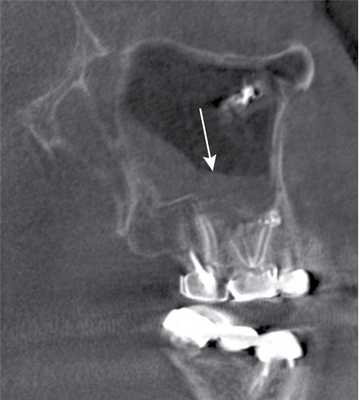

- После синус-лифтинга могут обнаруживаться зернистые затемнения в области дна верхнечелюстной пазухи

(Справа) На КЛКТ (поперечный срез) визуализируется зернистый трансплантат в лунке отсутствующего зуба. Контуры кости сохранены, резорбция и ремоделирование предотвращены. (Слева) На КЛКТ (панорамное реформатированное изображение), выполненной пациенту, которому планируется имплантация зубов, визуализируется трансплантат, введенный в дно верхнечелюстной пазухи («синус-лифтинг») с целью наращивания в значительной степени атрофированных задних отделов альвеолярного отростка. Визуализируются рентгенографические метки в области предполагаемой установки имплантов.

(Справа) На аксиальной КЛКТ у этого же пациента визуализируется зернистый материал в обла сти дна верхнечелюстной пазухи. Слизистая оболочка вокруг трансплантата утолщена. Кортикальные пластинки и контуры пазухи интактны. (Слева) На аксиальной КТ в костном окне определяется цветущая костная дисплазия (ЦКД) с поражением задних отделов нижней челюсти слева. Объемные образования, состоящие из цемента, нечеткие и неоднородные, и придают очагу зернистый вид. Обратите внимание на рентгенонегативный компонент по заднему краю очага.